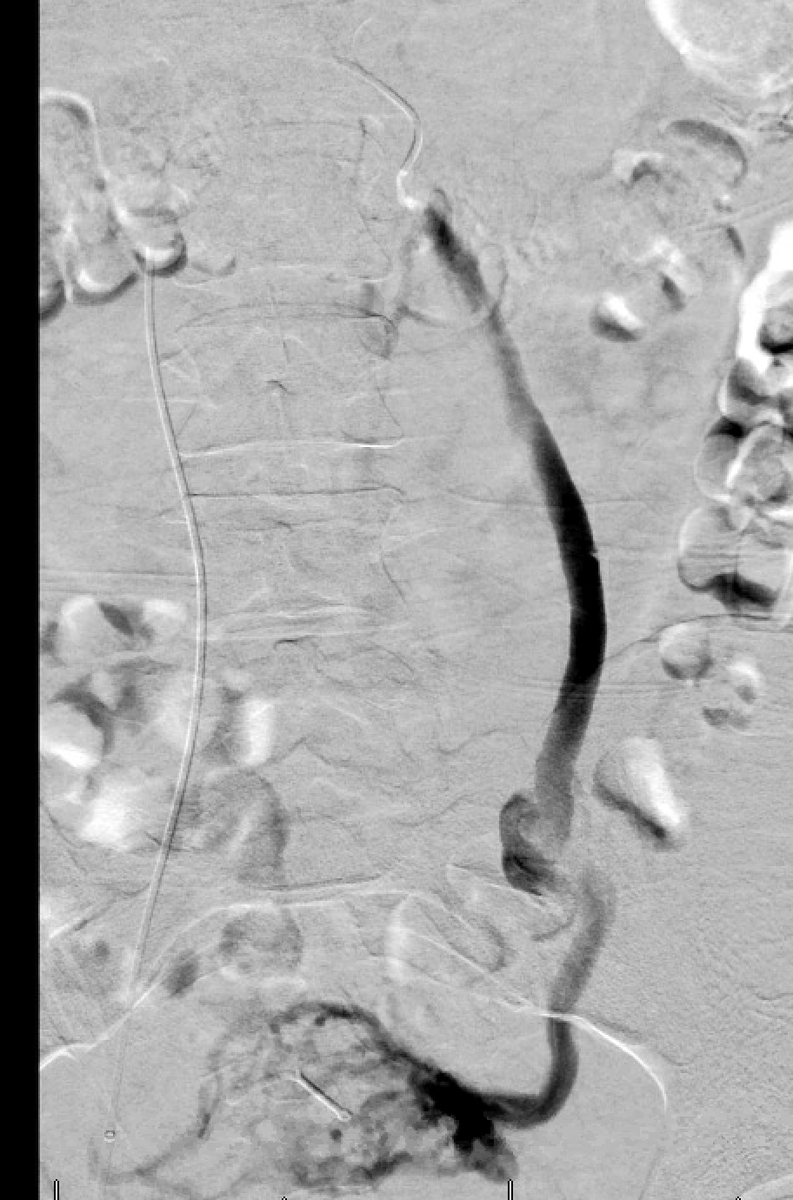

The day continued with a post renal biopsy bleed with active extravasation and a pseudoaneurysm, both of which were easily addressed with LAVA-18. Both patients are doing well after successful procedures. @SirtexMedical @thegestgroup